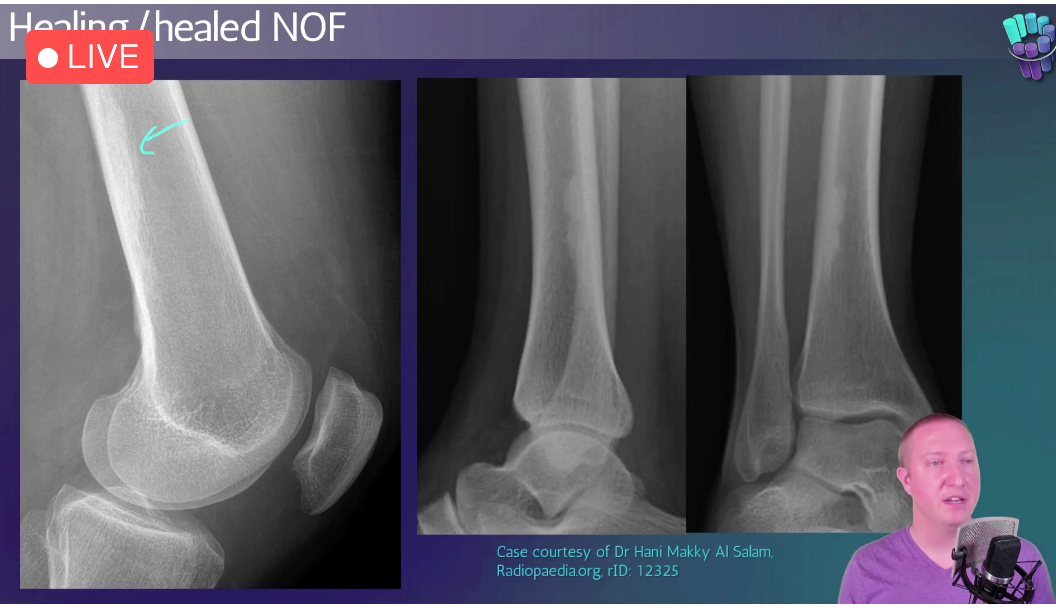

Healing/Healed NOF